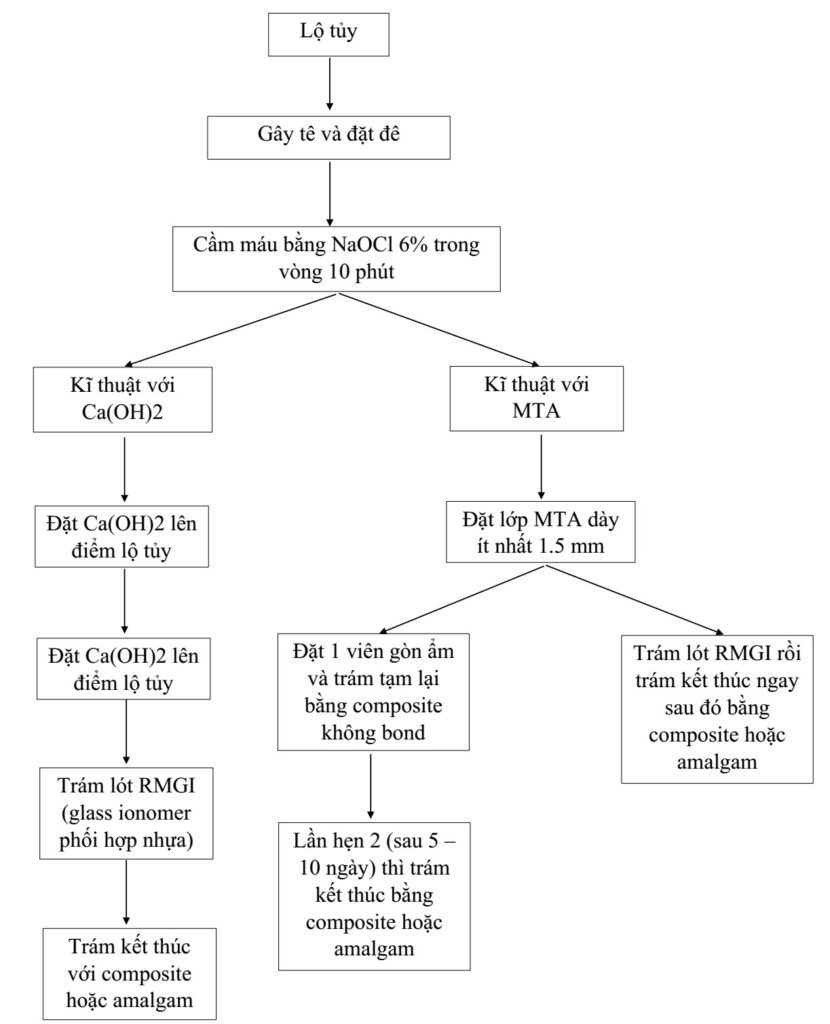

Kĩ thuật che tủy trực tiếp

Gồm kĩ thuật Ca(OH)2 và kĩ thuật MTA (canxi hydroxit technique and MTA technique). Mô răng sâu được loại bỏ bằng mũi khoan carbide #2 và cây nạo ngà (H10.13 và 10.10).

Kĩ thuật che tủy trực tiếp được mô tả trong sơ đồ dưới đây: